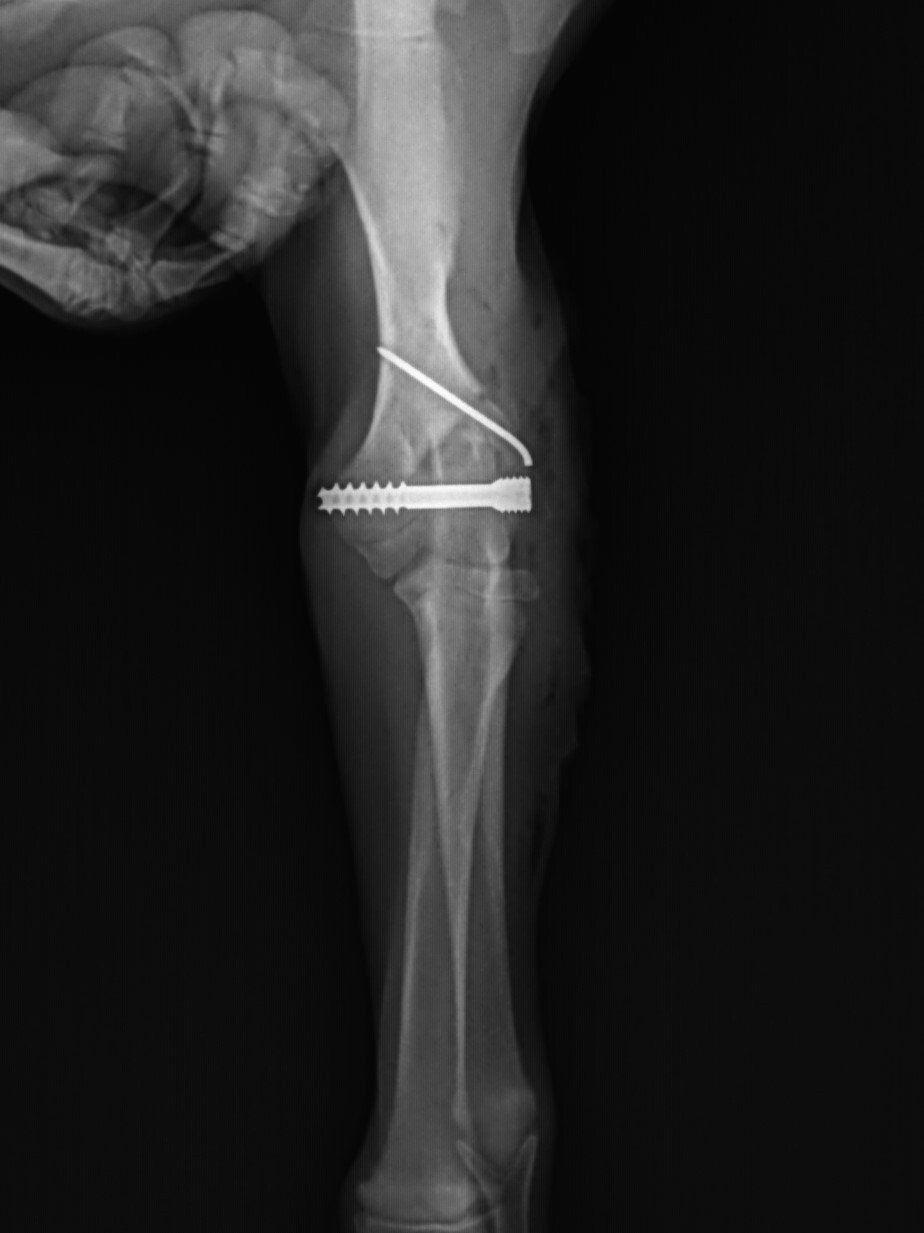

ButtonTPLO Surgery

Tibial Plateau Leveling Osteotomy (TPLO) is a procedure that modifies the geometry of the knee joint in dogs to allow a return to function after a CCL rupture. This is accomplished by making a semi-circular cut to the top portion of the tibia (shin bone). This top portion of the bone is then rotated to decrease the tibial plateau angle. This decrease in angle decreases or eliminates the instability and pain associated with having a ruptured CCL. Once the cut and rotation are made, a specialized plate and screws are placed to allow healing of the bone, which can take up to 12 weeks. The majority of the time this plate will stay in place for the remainder of your pet’s life. There are rare occasions in which the plate needs to be removed (infection, cold sensitivity, etc.). Once the bone is healed, the plate is no longer needed and can be removed with no adverse effects.

Below are x-rays of just a few orthopedic surgeries before and after that Dr. Gose has performed.